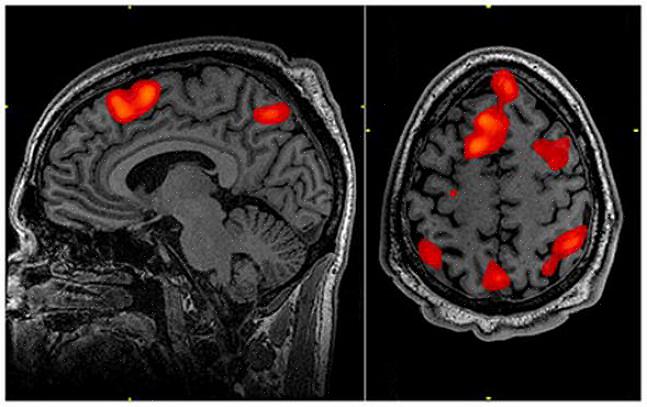

כדי לדעת איך המוח שלך מעבד גועל, אתה חייב בעצם לקחת בחשבון שני אזורים: האינסולה והמערכת הלימבית (השקדים וההיפוקמפוס).

האינסולה קולטת מידע מהמסלולים התחושתיים ושולחת מידע או גירויים למבנים אחרים, כמו המערכת הלימבית, הסטריאטום הגחון וקורטקס האורביטו-פרונטלי. נראה שהאזור הזה אחראי לחווית גועל, כמו גם לזיהוי ביטויי גועל אצל אנשים אחרים.

עד כה, מחקרים מדעיים טענו שגועל הוא חלק מאזורי מוח מסוימים, ותפסו תמונות של אותם אזורים שהם חשבו שהם מעורבים בהם. כעת, הודות לטכנולוגיות חדשות, כגון הדמיית תהודה מגנטית פונקציונלית, ניתן לראות בבירור כיצד המוח מעבד באופן דינמי גועל.

התוצאות גילו שהמוח עדיין מעבד את הרגש הזה 40 שניות לאחר שהסתכל על התמונות הלא נעימות. בנוסף, תמונות המוח הראו שלא רק חלק מהמוח פועל מול סצנה או חפץ מגעילים, אלא כמעט חצי ממנו.